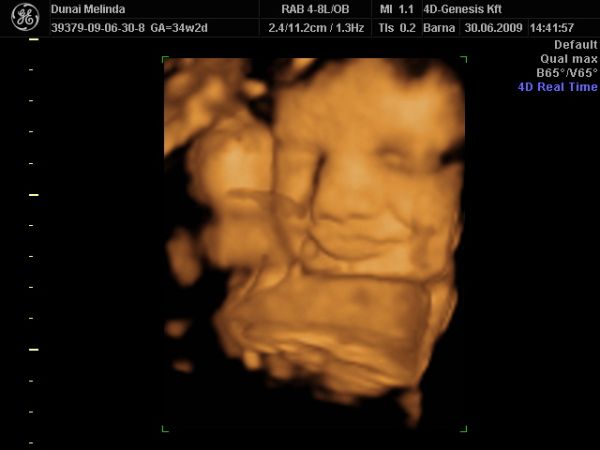

most elvileg megint vagy 10 hétig nem nézik Bogyót, 28-30. héten van megint kötelező UH. Iktass be közte egy 4D-t, ha tudsz. Én továbbra is javaslom a 4D Genesis-t, mi kedden megyünk másodjára. Olyan kedves az a nő, annyi mindent megnéz, nem csak a baba állapotát, hanem a tied is, és tuti nem enged úgy el, hogy ne hozza valahogy össze, hogy megkukkoljátok a lába közét, ha szeretnéd.

KépKép